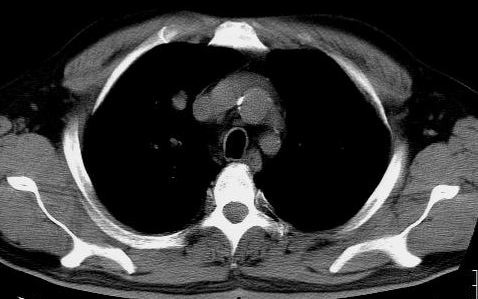

标题: CT15869:男性,71岁,因咳嗽而就诊,请讨论右上肺病变性质 [打印本页]

标题: CT15869:男性,71岁,因咳嗽而就诊,请讨论右上肺病变性质

患者,男性,71岁,因咳嗽而就诊,

典型的右肺中心性肺癌并纵隔淋巴结转移

右肺中心性肺癌并纵隔淋巴结转移可能性大!

病灶中等程度强化 还是支持肺癌诊断

考虑右肺中心性肺癌并右肺门及纵隔淋巴结转移。